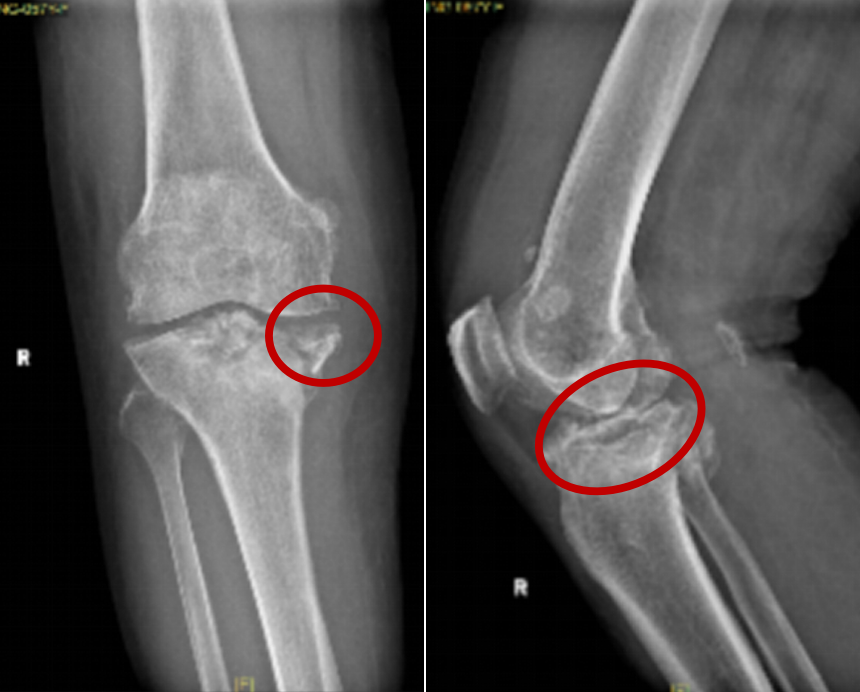

67 岁的张阿姨(化姓)多年备受膝骨关节炎的折磨,关节稳定性每况愈下,一起意外摔伤后,张阿姨选择了保守治疗,可没想到骨折愈合不佳,发展成了陈旧性骨折,还伴随明显的骨缺损,这让原本就不好的关节功能急剧恶化,疼痛加剧,连日常的起身、坐下都变得困难。

面对如此复杂棘手的病情,机器人辅助技术成为了关键力量。术前,张还添团队利用机器人系统,通过精准的三维建模技术对张阿姨的骨缺损范围、残余骨量分布以及力线偏移等关键数据进行测算。

在这些数据的基础上,团队制定了“人工膝关节置换 + 骨缺损修复”同步进行的创新手术方案,力求最大程度解决问题。

张还添介绍,骨折复位不佳或拖延治疗,关节面不平会加速软骨磨损成创伤性关节炎,还可能致内侧副韧带撕脱骨折,或使外侧副韧带松弛,破坏关节稳定性,让小手术变复杂,加重疼痛、畸形与功能丧失。对有骨关节炎者,摔伤更是病情恶化转折点,要警惕筋骨连锁损伤。